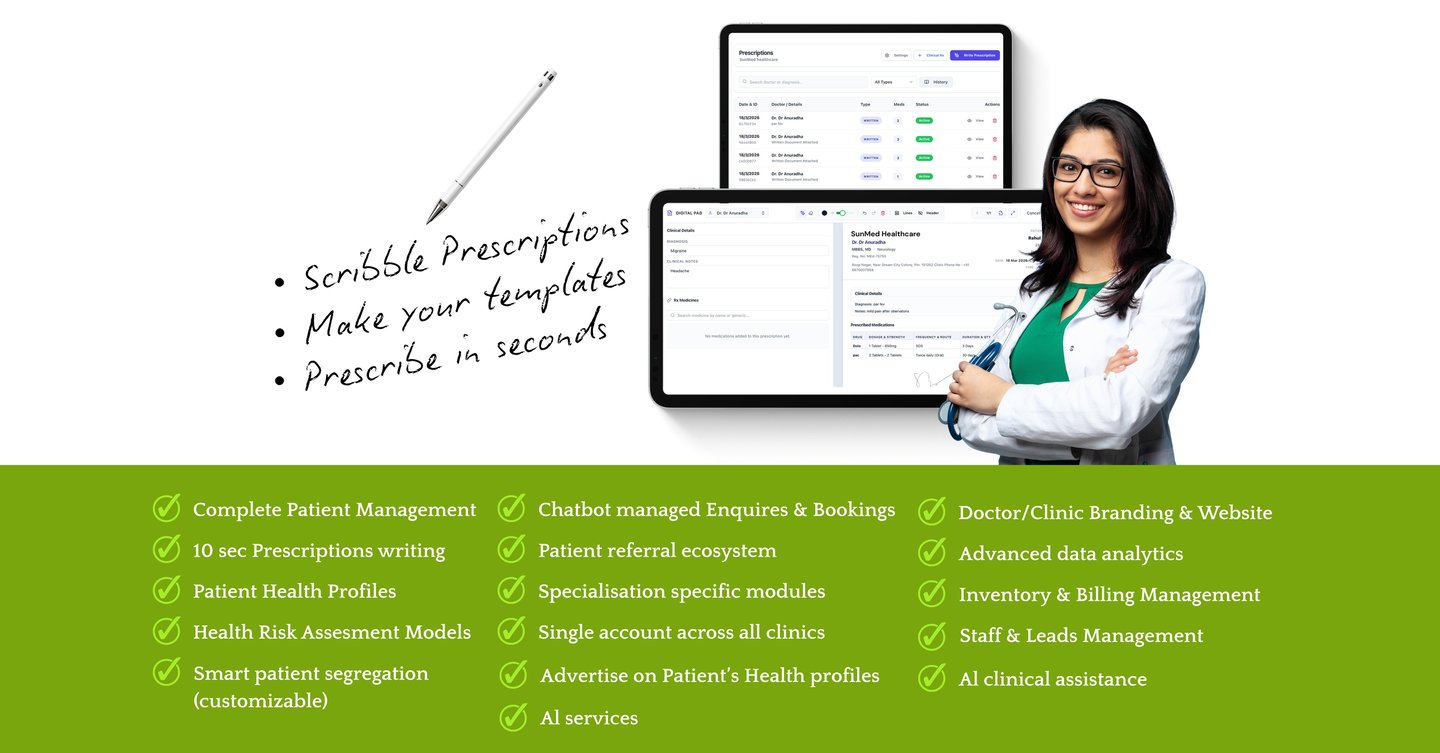

PHIA.CARE helps doctors run smarter Clinics / Polyclinics with AI-assisted prescriptions, instant risk reports, and fully digital patient management—so you focus on treatment, not paperwork.

Time consuming prescription writing and managing past prescriptions.

THE SOLUTION

PHIA.CARE is your digital clinic assistant.

It simplifies everything—from patient entry to follow-up

Saves time.

Easy OPD workflows in few taps.

AI assisted health summaries & prescription writing

Phia.Care brings all patient data—visits, prescriptions, reports, and history—into one seamless platform, reducing manual work and saving time.